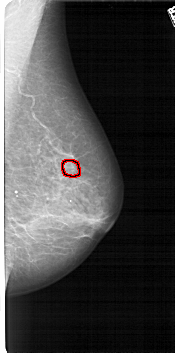

FILE: A_1118_1.RIGHT_MLO.OVERLAY

TOTAL_ABNORMALITIES 1

ABNORMALITY 1

LESION_TYPE MASS SHAPE IRREGULAR MARGINS SPICULATED

ASSESSMENT 4

SUBTLETY 2

PATHOLOGY MALIGNANT

TOTAL_OUTLINES 1

BOUNDARY